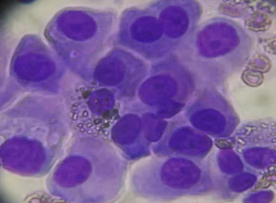

何志勇主任介绍,经过再次对肿瘤活检和检验检测,发现李先生仍然存在EGFR突变的肿瘤克隆。

“可能肿瘤还依赖EGFR信号通路,提高三代EGFR-TKI给药浓度是可能的有效方法之一。”

何医生介绍,三代EGFR-TKI伏美替尼由于化学结构上的优化,具备提高药物浓度而不增加副反应的可能,国内外有相似的研究报道。因此,建议李先生开始口服“双倍剂量伏美替尼”靶向治疗。令人欣喜的是,1个月后复查,李先生肺部及肝脏转移灶较前明显退缩,疗效评价达到部分缓解。